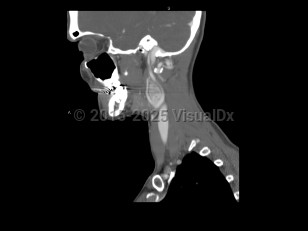

Carotid body tumor

Carotid body tumors / paragangliomas are tumors that arise from cells of the neural crest, particularly in the head and neck, along the carotid body. They can involve other locations. They can present as painless masses but, depending on their location, can cause nerve root compression, pain, and cranial nerve palsies. Treatment involves surgical resection.